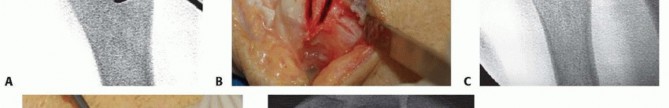

We begin with a longitudinal incision over the distal and middle thirds of the ulnar diaphysis. While a dorsal approach is described, we strongly prefer the volar-ulnar approach. The incision is placed directly over the palpable subcutaneous border of the ulna, typically extending 8 to 10 centimeters. We carefully deepen the incision through the subcutaneous tissues, remaining acutely vigilant for the dorsal sensory branch of the ulnar nerve (DSBUN). This critical nerve typically crosses the operative field from volar to dorsal approximately 5 to 8 centimeters proximal to the ulnar styloid. It must be meticulously identified, mobilized, and protected with vessel loops throughout the procedure to prevent painful post-operative neuromas.

The deep fascial interval is developed between the flexor carpi ulnaris (FCU) volarly and the extensor carpi ulnaris (ECU) dorsally. We elevate the FCU muscle belly and retract it volarly, exposing the palmar and ulnar aspects of the ulnar diaphysis. Here, surgical discipline is paramount: periosteal elevation must be strictly limited to the footprint of the plate. We use a sharp elevator to clear only the necessary bone, preserving the dorsal and interosseous soft tissue attachments. This rigorous adherence to minimal periosteal stripping is the primary defense against devascularizing the bone and precipitating a nonunion.

With the diaphysis exposed, we apply the dedicated cutting jig. The jig is temporarily fixed to the bone using bicortical screws. We utilize a sharp, cooled oscillating saw to execute the osteotomy. Copious cold saline irrigation is non-negotiable during the cutting phase to prevent thermal necrosis of the bone ends, which is a major contributor to nonunion. We make the proximal cut first, followed by the distal cut, removing the precisely templated wafer of bone. The oblique nature of the cut (usually 45 degrees) allows the bone ends to slide seamlessly together without rotational malalignment.